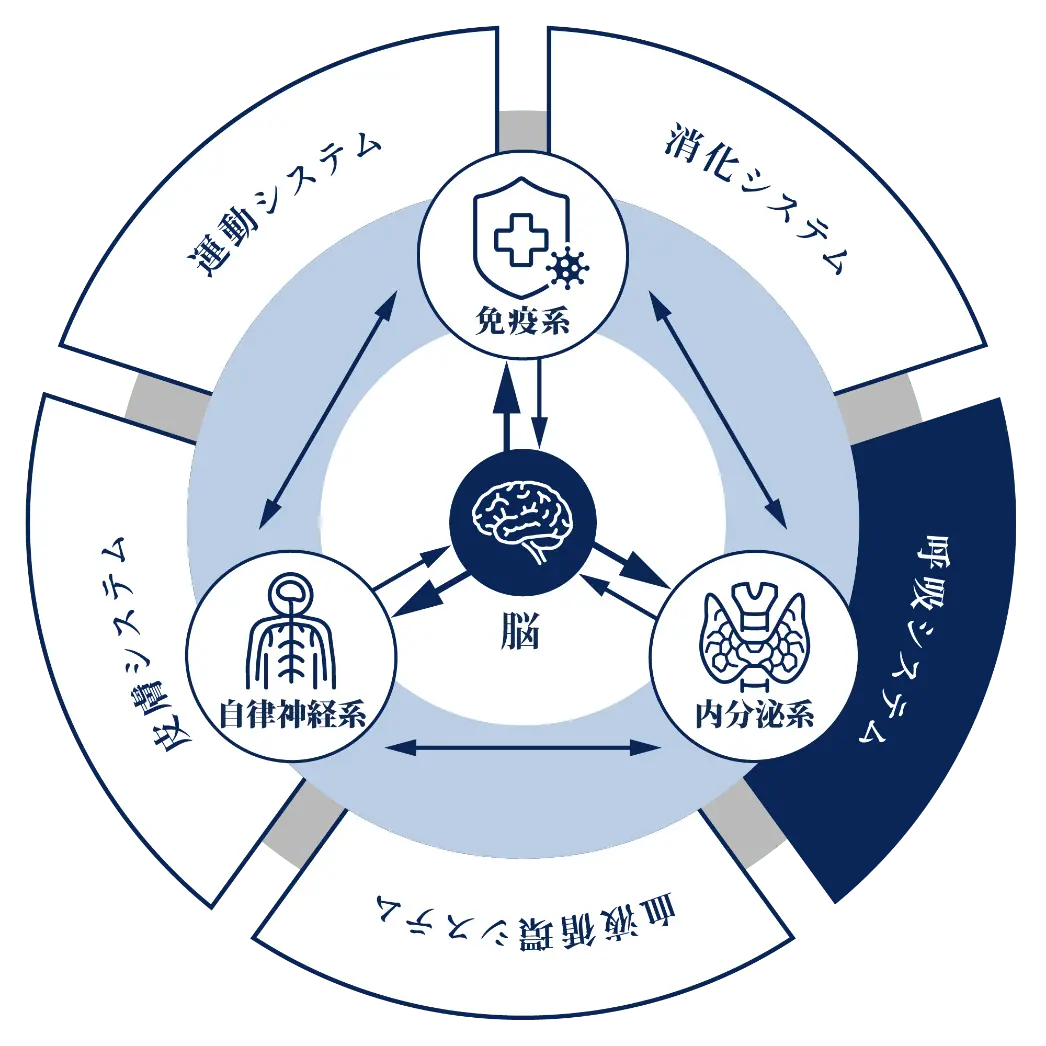

呼吸は自律神経によって制御され、酸素が不足すると脳が反応し、呼吸の深さや頻度を調整します。

呼吸の調節と自律神経

呼吸の過程は自律神経系によって制御されています。

自律神経は、血液中の酸素と二酸化炭素のレベルを監視し、呼吸の深さや頻度を調整します。

もし体内の酸素が不足すると、脳はその不足を感知し、できるだけ早く調整を行います。